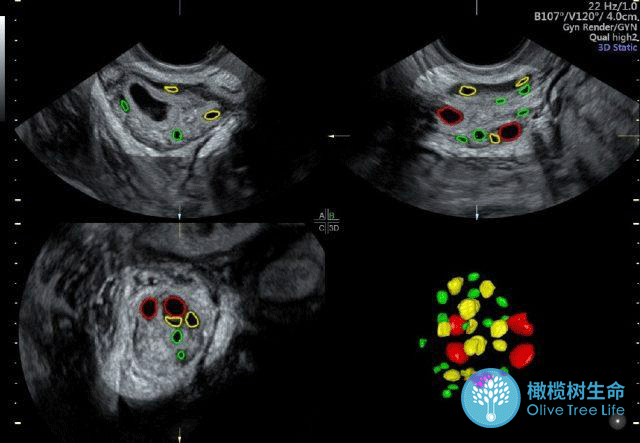

那我们如何查看自己的“余额”?怎么判断卵巢是否健康?别担心,橄榄树生命小橄榄今天就来告诉你!

查看“家底”和判断卵巢健康的指标